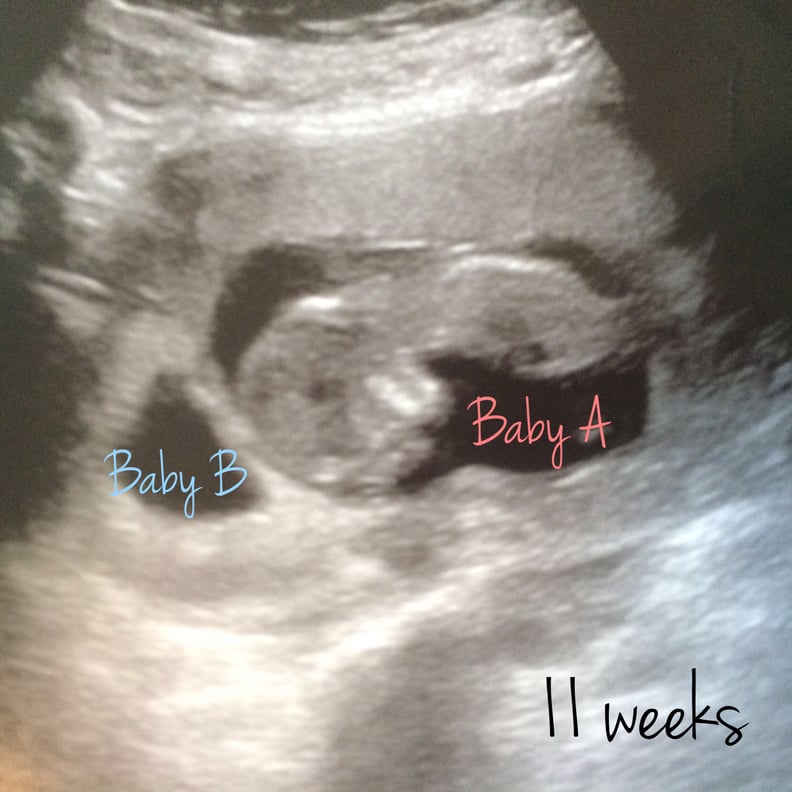

From www.popsugar.com

What It's Like to Experience Vanishing Twin Syndrome POPSUGAR Family What Does A Vanishing Twin Look Like On An Ultrasound this article will discuss how vanishing twin syndrome is detected on an ultrasound, the symptoms associated with having a. vanishing twin syndrome (vts) is a miscarriage that causes a pregnancy involving twins to become a. how will i know if i have a vanishing twin? Most often, a vanishing twin is diagnosed during an ultrasound. If your. What Does A Vanishing Twin Look Like On An Ultrasound.